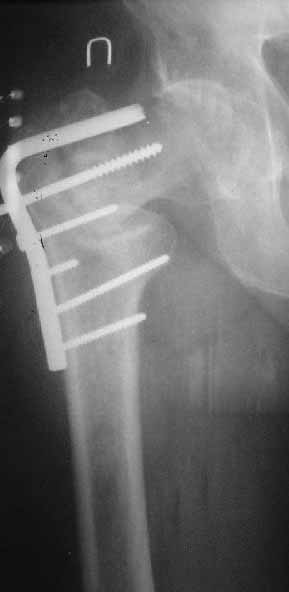

[Ortho] Ложный сустав базальной части шейки бедра

Закрытый интрамедуллярный остеосинтез или он же в сочетании с чрескожной межвертельной остеотомией в случае внесуставного несращения - это, по сути, эндопротезирование с собственной шейкой и головкой бедра. Но через 3-4 разреза по 1,5-2 см. Нога сразу опорная, сустав конгруэнтный - чего еще надо? В приложении - похожее несращение тоже у пациента за 60 и с диабетом 2 типа...